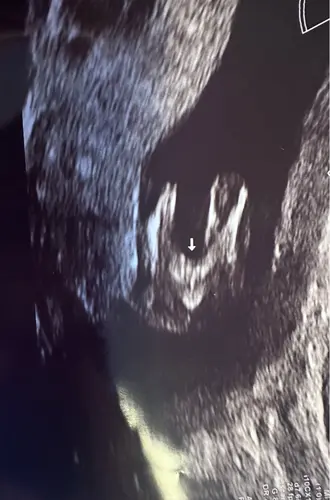

Yes is een jongetje! Had precies dezelfde foto en gisteren te horen gekregen dat het een jongen is. Met 14+5 dagen

Maar inwendig krengen we dit beeld als eerste te zien, 2 benen met een puntje in het midden.. de verloskundige zei er niks over omdat wij het niet willen weten. Maar nu denk ik dus whaha zou het dan toch echt zo zijn!🤣🙈. We hopen stiekem zelf namelijk als gezin wel op een jongen!🥰

Dit beeld heb ik ook gezien 🤭 mijn gyno zei “we kijken deze echo niet naar het geslacht, ze hebben nu allemaal een verdikking” ja ammehoela 🤣 ik heb al een jongen dus herkende dit beeld direct 😜